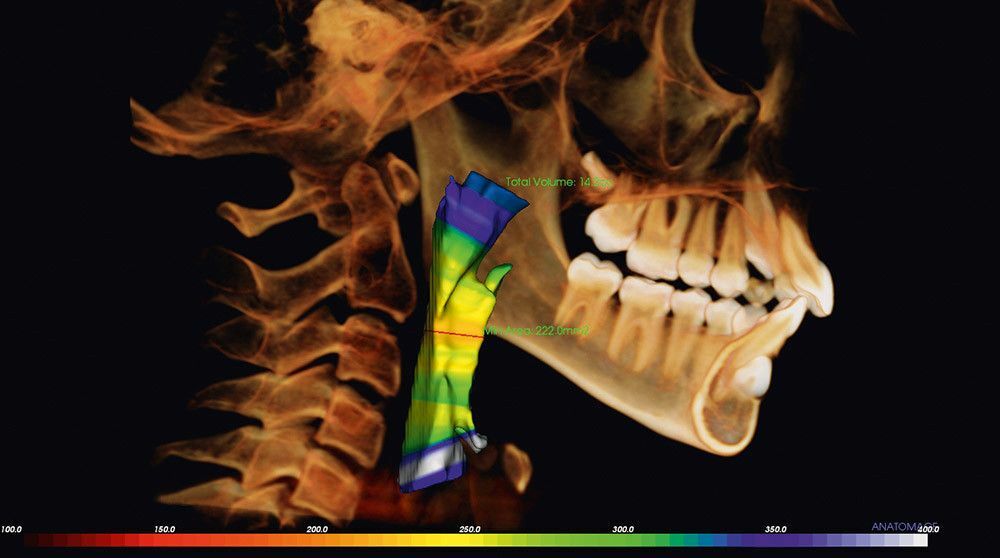

Исследование дыхательных путей: визуализация узких дыхательных путей